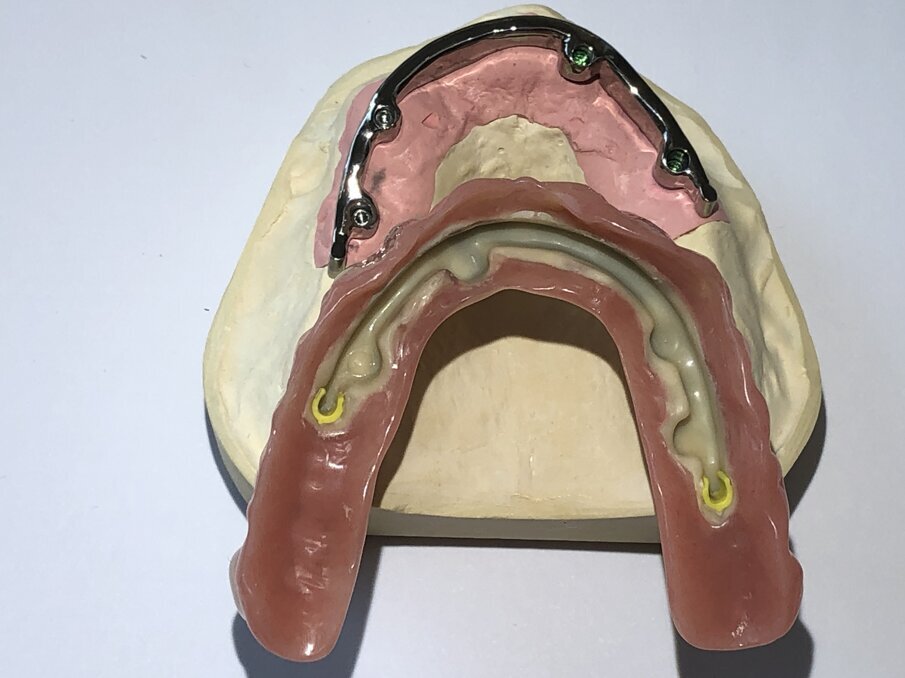

Een andere staafconstructie is de individueel handmatig gefreesde staafconstructie. Een identiek secundair deel van metaal is bevestigd in de prothese en verankerd met behulp van één of twee precisie-kunststoffen-onderdelen (afbeelding 8, 9 en 10, de groene delen).

Om de staaf een goede houvast te geven en het voor patiënten eenvoudiger te maken om de prothese in en uit te nemen, wordt het secundair gefreesde metalen deel volledig met kunststof bedekt. Wij kunnen dit realiseren door in plaats van twee à drie kleine kunststof onderdelen, een volledig secundair deel in kunststof gefreesd met CAD/CAM in het secundaire metalen deel te lijmen (afbeelding 9).

Het gehele secundaire deel in de prothese zit op de staaf met behulp van de gefreesde kunststofonderdelen en zorgt voor een comfortabele grip van de prothese. Om de houvast van de prothese te versterken, worden er ook nog twee kunststof precisie-onderdelen distaal in het gefreesde kunststof deel ingebracht (afbeelding 10, het gele gedeelte). In vergelijking met de klassieke staafconstructie zorgt deze innovatieve constructie ervoor dat de prothese een stevige houvast heeft, zodat de patiënt soepel en moeiteloos in alles kan bijten.